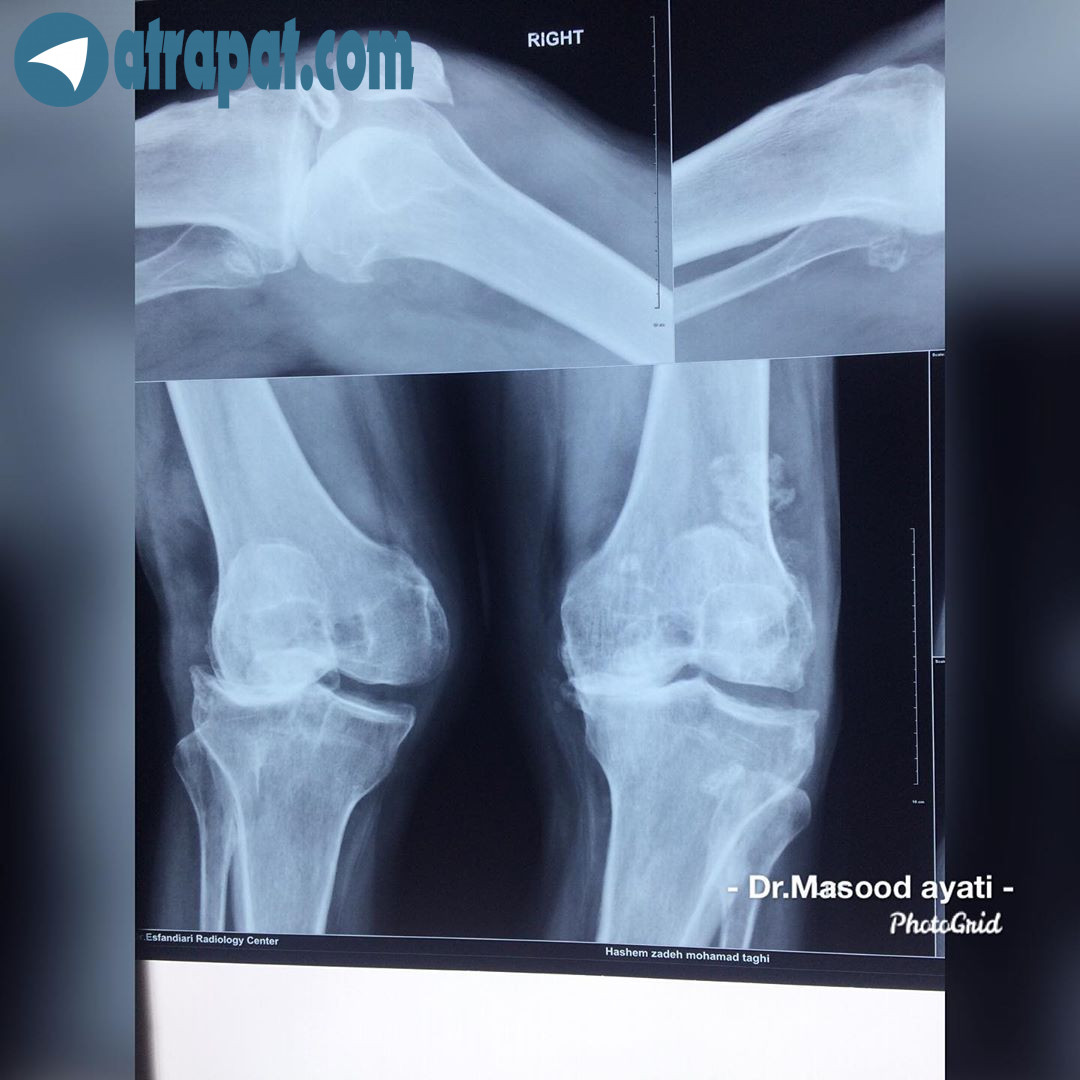

بيمار خانم ٥٨ ساله كانديد تعويض مفصل زانو (پروتز زانو),رهايي از رنج درد و ناتواني در راه رفتن تنها بعد از ١٢ روز بعد عمل (بخيه ها تازه كشيده شده )كنگره انجمن جراحان ارتوپديبيمار اقاي ٧٠ ساله كه با شكايت زانو درد شديد ،عدم توانايي در راه رفتن و كارهاي روزمره مراجعه نموده كه با تشخيص داده شده بيمار دچار آرتروز و ساييدگي مفصل شديد به همراه آن انحراف زانو نيز ميباشد.

(عمل تعويض مفصل هر دو زانو و رهايي از درد و ناتواني )٤٨ ساعت بعد از عمل تعويض مفصل هر دو زانو

48 hours after total knee Replacementرهايي از درد و ناتواني و كارهاي روزمره تنها هفت روز بعد از عمل تعويض مفصل هر دو زانو ‏Relief from pain and disability after only seven days knee Replacementممنونم از همه ...بيمار خانم ٦٥ ساله كانديد عمل تعويض مفصل هر دو زانو ،بهبودي كامل بعد از٧ روز از عمل جراحيبيمار اقاي ٦٥ ساله